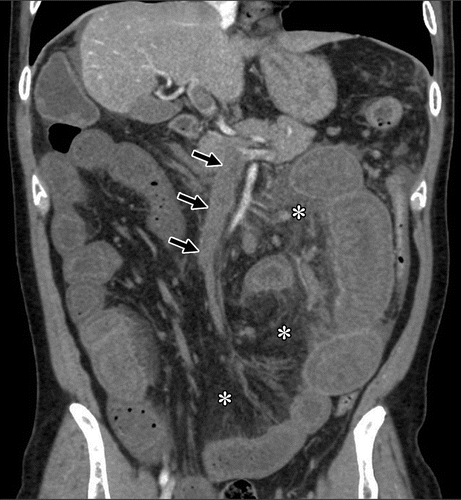

• Duplex Ultrasound, CT Angiography, or MR Angiography for precise vessel imaging